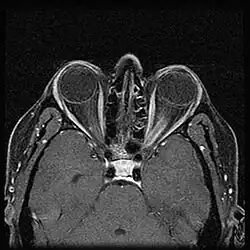

MRI of a patient with ONSM

When ONSM is suspected, MRI of the brain or orbits should be performed. This will usually show characteristic findings and confirm the diagnosis.[5]